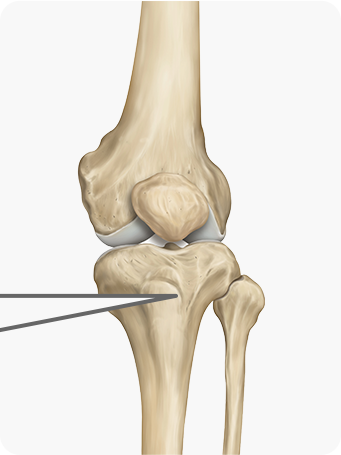

치료과정

종아리뼈 일부를 절골한 후, 수술 기구를 이용하여 필요한 각도만큼 뼈를 벌려

금속판과 나사를 이용하여 고정합니다.